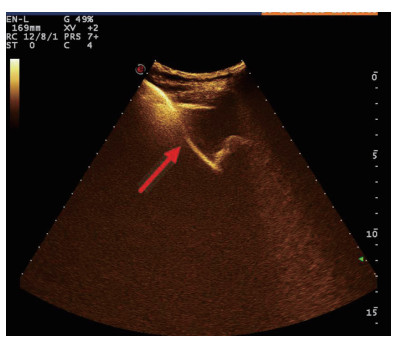

| 图 3 经引流管造影胆囊超声显像,二维图像(左),造影图像(右) |

术后再次经肘静脉超声造影同时经引流管超声造影:PTGBD后,再次经肘静脉快速团注SonoVuel 2 mL,在造影成像模式下进行观察肝脏被膜、胆囊床穿刺路径有无造影剂外渗,腹腔内有无外渗凝聚的造影剂,判断有无活动性出血及出血程度,如判断出血速度快、出血量较大,考虑动脉性出血,及时改为开腹或腔镜手术止血。PTGBD术后经引流管超声造影,置管成功后快速抽出胆囊内残留胆汁,减轻胆囊压力后,在超声造影模式下直接经引流管注入配制待用的稀释声诺维造影剂20 mL,实时动态的观察造影剂在胆囊腔内的充盈范围(图 2、3),评估引流管的通畅程度及引流范围、观察其在胆囊腔内的位置走形及卷曲情况、观察胆囊周边及腹腔内有无造影剂外渗。如患者腹痛症状加剧,结合经引流管超声造影判断有胆汁漏出表现,应持续监测观察患者生命体征及保守治疗效果,必要时及时改行开腹或腔镜手术治疗。

超声造影是利用超声造影剂微泡(本组应用的是声诺维超声造影剂微泡)在低机械指数声波照射下发生共振,产生线性及非线性谐波回声信号,形成造影增强图像的技术,是近年来新兴的超声技术,具有实时、可连续观察、无辐射、可重复性好、毒不良反应少等优势,为临床提供了全新的诊疗手段[14]。经肘静脉注入的标准配置超声造影剂是一种血池造影剂,可以反映组织的血流灌注情况同时亦被广泛应用于肝、脾、肾等实质性脏器破裂的诊断,其诊断的敏感性及特异性均明显优于二维超声,且与增强CT有较好的一致性[15-16]。本组病例术前经肘静脉注入标准配置造影剂后,胆囊壁均显影增强,胆囊穿孔及周边积液处表现为造影无充盈区,穿刺置管后再次静脉路超声造影,迅速发现术后出血部位且可敏感评估是否为活动性出血(经手术证实)。除1例因活动性出血中转腹腔镜手术外,其余32例置管成功后经引流管口注入稀释造影剂20 mL(1:200稀释),评价引流管位置、引流范围及是否出现胆汁外漏取得良好效果,所有引流导管均能够清晰显示引流导管置入路径、引流管形态及引流范围,引流管置入恰当者,头端位于胆囊内,全管显影清晰,造影剂弥散区域与胆囊大小吻合; 置管后胆汁漏出者,可见造影剂沿引流管周边渗出[17-18],本组中3例出现造影剂外渗,其中两例渗出范围局限于胆囊床附近,未渗出至游离腹腔,患者腹痛症状稍有加剧,经胆囊减压及对症处理后好转,其中1例见造影剂渗出至肝肾间隙,患者腹痛症状加剧明显,考虑置管位置不当,余行急诊腹腔镜手术治疗,术中证实为系膜胆囊,且可见引流管侧孔部分外露。笔者的经验是,术前选择静脉路超声造影有助于对胆囊情况的评估及穿刺点的选择,术中正确选择穿刺针的入路有利于提高穿刺引流的成功率。首先是胆囊穿刺部位的选择应选择在靠近胆囊颈侧,此处胆囊位置比较固定,受体位影响较小,且胆囊床结缔组织较为固定,有助于将漏出胆汁包裹局限,其次是进针方向与胆囊床尽可能保持垂直,减少进针位置的偏移,同时置管成功后应即刻尽量抽尽胆囊内的感染性胆汁,生理盐水冲洗后行经引流管稀释超声造影有助于判断置管位置、引流范围及是否出现胆汁漏出,减少不必要的并发症发生率。穿刺引流后可以根据患者的营养状况待窦道形成稳定后择期拔除引流导管。对全身情况改善适合手术治疗且有手术意愿者可以考虑择期胆囊切除术。